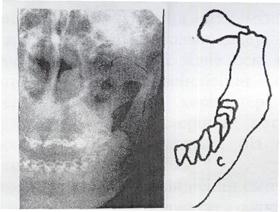

Клиникалық болжауды рентгенограмма арқылы дәлелдеу қажет. Рентгенограмма сынықтың және жарқыншақтардың ығысу дәрежесін, тіс түбірінің сыныққа қатынасын сипаттайды (80-сурет). Әдетте, екі рентгенограмма жасалады: бірі — тік, екіншісі — бүйірден. Егер мүмкіншілік болса ортопантомограмма жасаған жөн. Төменгі жақтың буын өсіндісі сынса, томограмма көп мәлімет береді. Дәрігер клиника-рентгенологиялық көрсеткіштердің негізінде дұрыс топикалық нақтама қойып, емдеу жоспарын жасайды.

80-сурет. Төменгі жақ сүйегінің сынығы